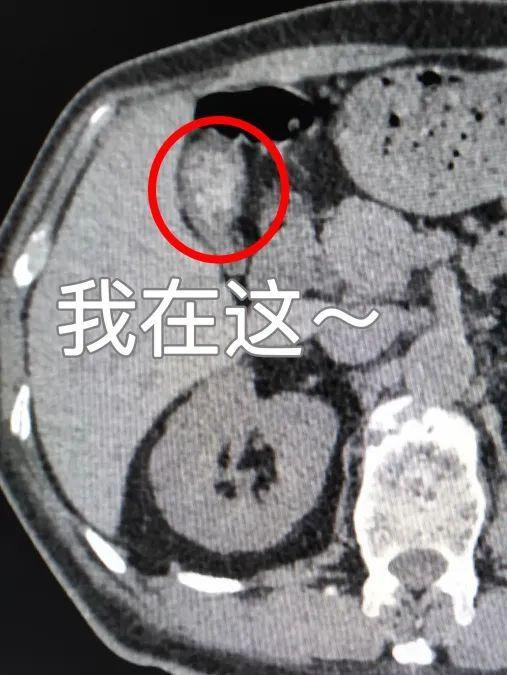

胆囊阳性结石

胆囊阳性结石就是胆色素类结石(CT上表现为高密度):CT表现为高密度,CT值在50Hu以上,单发或多发,形态、大小各异,泥沙样结石常沉积在胆囊下部,呈高密度,与上部胆汁形成液平面。